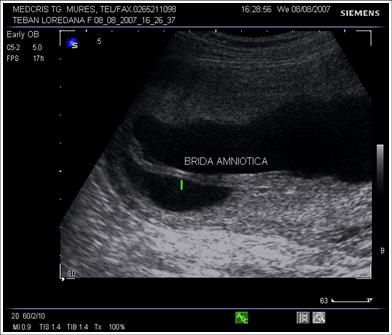

Benzi amniotice: linii ecogenice in lichidul amniotic intre

placenta si peretele uterin, unele produse de separarea partiala a amniosului

de chorion, altele produse de o sinechie uterina sau un sept uterin incomplet.

De obicei nu constrang miscarile fetale si nu sunt atasate fatului.

Fig. nr.226. Brida amniotica la o sarcina de 16 saptamini

Sindromul de banda amniotica ( ADAM = amniotic deformity, adhesions, mutilations) se datoreaza unei rupturi precoce de amnion, urmata de separarea amniochoriala si punerea in contact a fatului cu chorionul. Atat chorionul expus, cat si restul suprafetei amnionului, produc bride mezodermale care se extind spre fat , dupa ce chorionul absoarbe lichid amniotic.

Incidenta intre 1/1200 si 1/10000 de nascuti vii.

Diagnostic ecografic: tipic oligohidramniosul este asociat cu benzi ecogene intre placenta sau peretele uterin si fat , cu restrictia miscarilor fetale.[9]

Spre deosebire de anomaliile genetice fetale, anomaliile induse de benzile amniotice sunt asimetrice.

Cazurile severe implica amputatii de degete sau membre, strangulatii ale creierului sau chiar prin compresie de cordon ombilical, moarte fetala in utero.